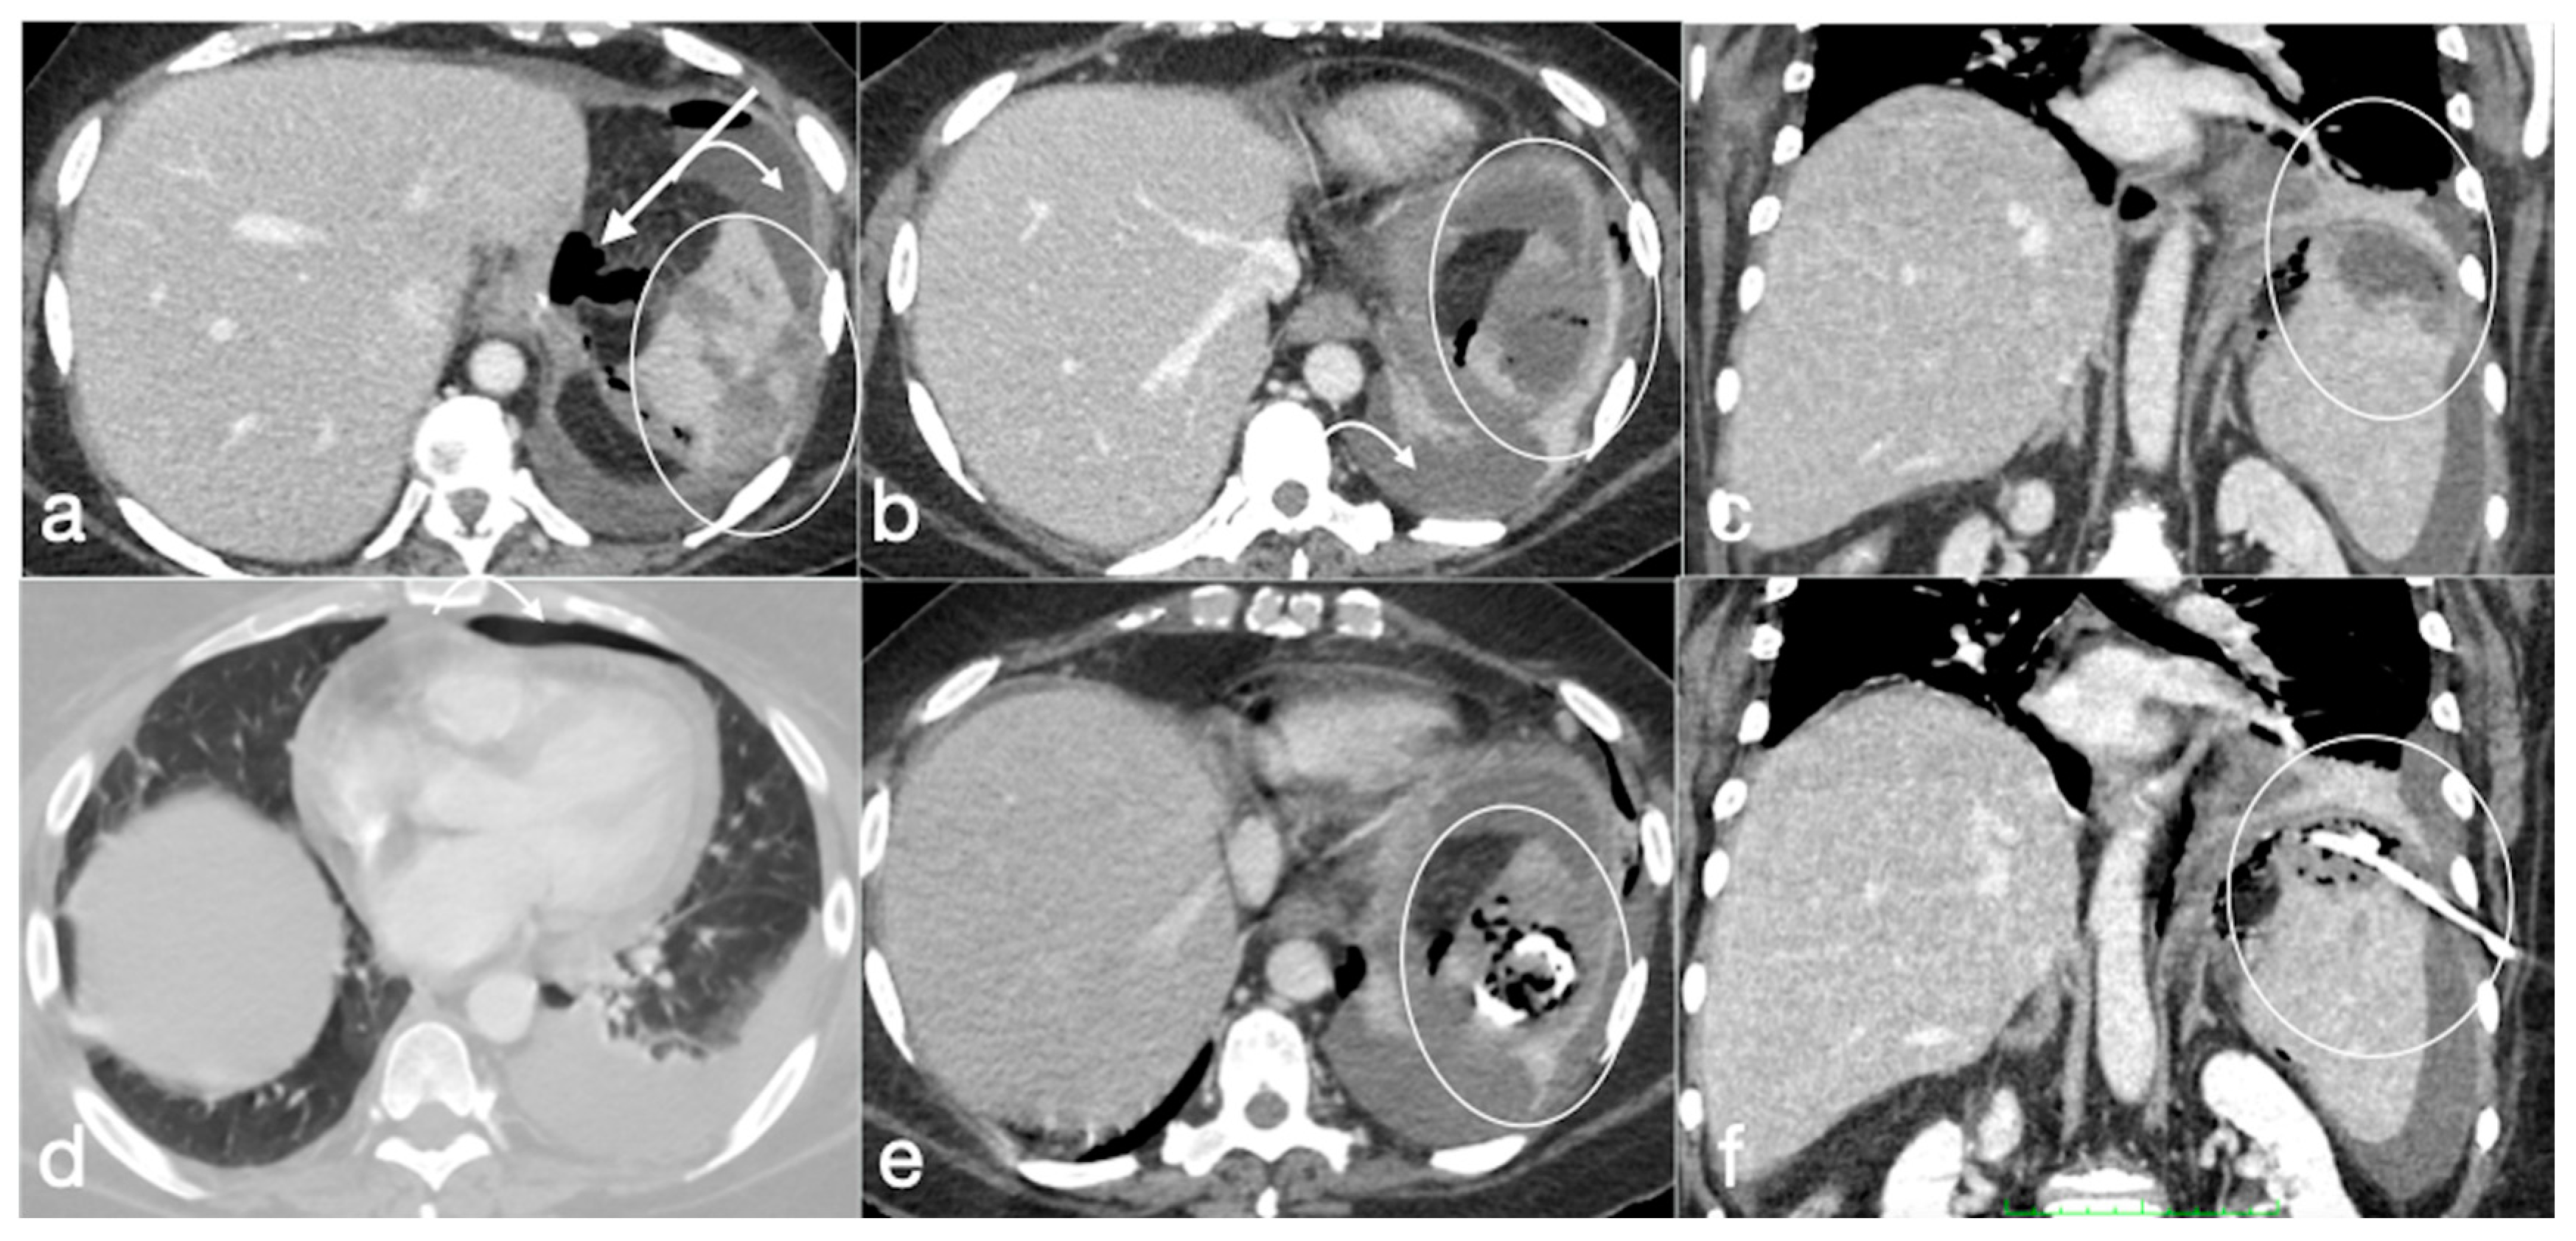

Figure 20. Patient 2. Suture leak with spleen abscess after sleeve gastrectomy. A 48-year-old patient underwent sleeve gastrectomy and complained in the following days of abdominal pain, fever, and dyspnea. At the first CT examination is seen the leak (a, axial view, straight arrow), free peritoneal fluid (a, curved arrow) and inhomogeneous enhancement of the spleen (a, circle). In more cranial scans, a splenic abscess is seen (b, circle) associated with the reactive pleural effusion (b, curved arrow), and the coronal view (c) further clarifies the finding (c, circle, splenic abscess). It was decided that the patient should be managed with percutaneous drainage of the splenic abscess. The patient came back after the drainage positioning, with chest pain and dyspnea (df) and at CT the left anterior pneumothorax (d, axial view, curved arrow) was detected due to the drainage positioning, which is actually in the splenic abscess (e, axial view, circle). However, in its course it crosses the left diaphragm (f, coronal view, circle).